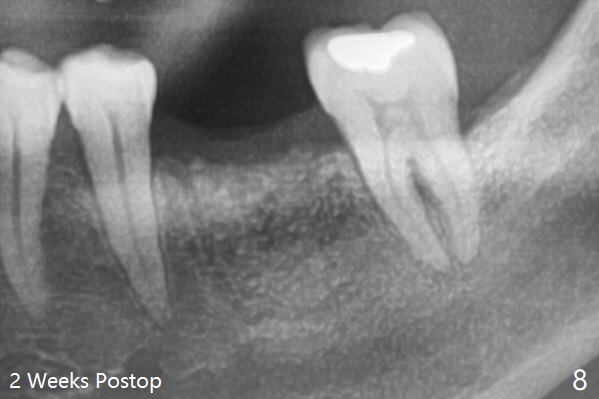

A 62-year-old man (smoker, 1.5 packs a day) has had no dental visit for 12.5 years (Fig.1). His chief complaint is pain at #19 after eating popcorn. The septal bone resorbes (Fig.2,3 *) with granulation tissue between the mesial and distal roots (Fig.4,5 *). Although there is no bony wall defect, the socket is single and large (9x9 mm, Fig.7). The largest (8 mm) cylindrical implant should not be able to obtain primary stability. The biggest challenge for immediate implant is ambiguous the Inferior Alveolar Canal (Fig.1,3 red dashed line). If there were no financial or time issue for immediate implant, CBCT should have been taken. Socket preservation is done instead with Vanilla graft, Human Amniotic Chorion Allograft (membrane) and Osteogen Plug (Fig.6). If he returns for SRP and implant, perform flapless bone expansion for osteotomy. When the patient returns 14 d postop, #19 socket is healing and filled with bone graft (Fig.8 (panoramic X-ray)). When he returns 14 months postop, the socket heals (Fig.9, as compared to Fig.6).